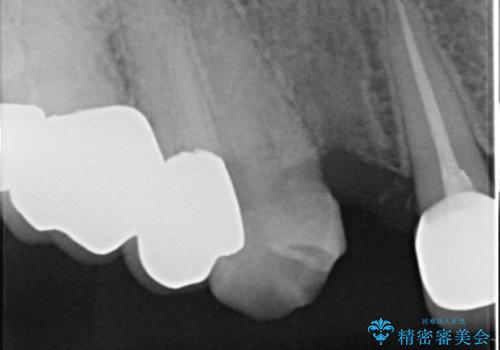

クラウン下に再発した深い虫歯 インプラントによる機能回復

- 45万円(ストローマンインプラント・骨造成・チタンカスタムアバットメント・ジルコニアクラウン)費用は治療当時の料金となります

前歯のインプラントを仕上げるには骨や歯ぐきの条件を整えることが肝要です。